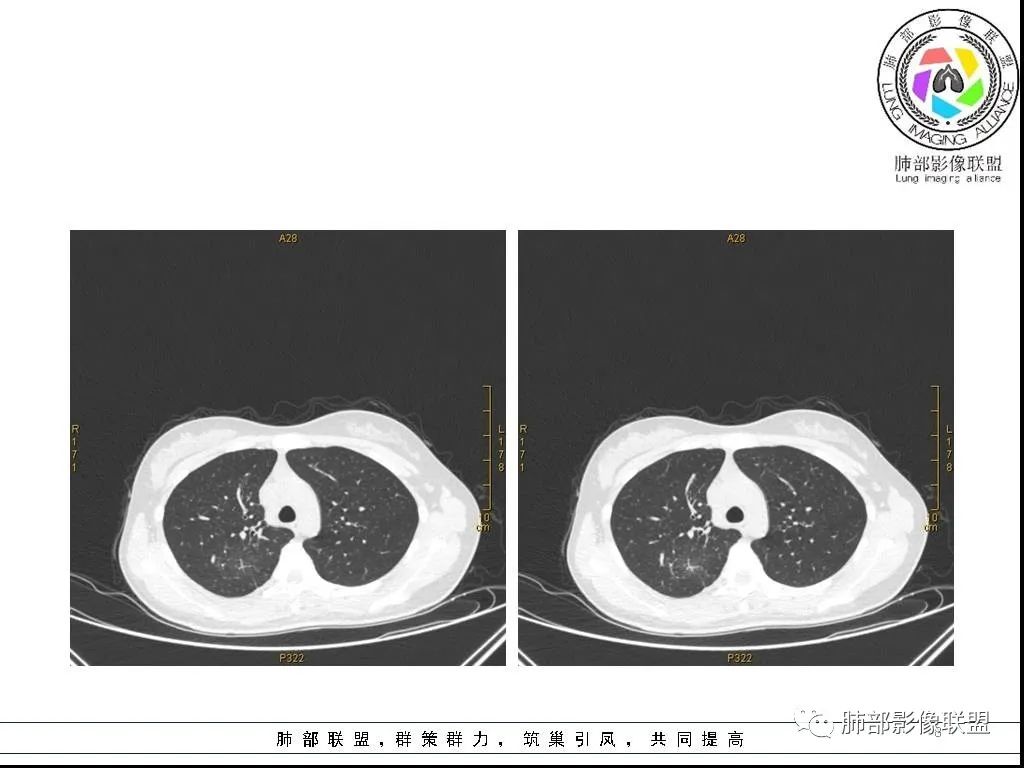

右肺炎症性病变1例CT影像讨论

年轻女性,病程长,咳嗽少痰4个月,辅检未见特殊,CT:右肺团块影,跨叶,主体在下叶背段,外大内小,边缘以膨隆为主,部分平直内收,深分叶,周围有模糊晕,可疑卫星灶,胸膜增厚,糊墙,支气管近端部分进入,粘液栓,有坏死空腔,内壁光整,部分血管侵蚀,强化不均,延迟,明显;同侧R10、7、R4淋巴结肿大,考虑肉芽肿炎,结核,需要与肿瘤鉴别:16岁,女性,诊断肿瘤需要勇气,跨叶多见于炎性,需要进一步活检。

右肺上叶后段及下叶背段条带状影,病灶边缘整体以收缩平直为主,部分膨隆,延支气管由外朝内蔓延,不受叶段限制,外围大,近肺门区小,其周散在结节状卫星灶及部分GGO,中度不均质强化,血管穿行受侵,邻近胸膜反应性增厚。青少年慢性病程,咳嗽咳痰,总体倾向炎性肉芽肿,结核可能性大。

青少年女性,咳嗽咳痰4个月,血沉快,ppd阴性。右肺上叶后段及下叶背段可见一长条块影,边缘平直,有收缩及凹陷,局部有膨隆,长轴与支气管平行,近段支气管似有粘液栓阻塞,血管进入后有破坏,周围有磨玻璃影及少许卫星灶,中度不均匀强化,局部胸膜增厚,少量积液,考虑炎性肉芽肿,肺结核可能性大,鉴别op,淋巴瘤,肺癌。

16岁女性,咳嗽,咳痰4月,无发热,白细胞不高,炎性指标(CRP,PPT)不高,血沉增高(75mm/h)。影像表现:右肺胸膜下不规则肿块影,边缘平直,U型凹陷,桃尖征为主,纵隔窗部分层面似有多个结节融合感,近端支气管扩张,堵塞,局部呈鬼脸样改变。边缘可见长短不一毛刺影,周围见晕征,远端见多个小结节卫星灶。胸膜大面积反应性增厚,增强后不均匀中度渐进性强化,局部干酪样坏死可能(CT值-32~-15)内部血管走行较正常,破坏不明显。 医学百科网 | YxBaike.Com

16岁女学生,咳嗽咳痰4个月。右肺上叶后段、下叶背段跨叶长条状不规则软组织密度影,周边可见散在小结节与磨玻璃影,与胸膜宽基底相连,胸膜增厚。增强明显渐进性不均匀强化,内部部分血管管壁毛糙,於曲破坏,近肺门见条状无强化影—粘液栓?考虑为肉芽肿性病变,结核可能。 医学百科网 | YxBaike.Com

这个病例的特点:病灶贴近斜裂内侧区域,范围较大,直达肺门区。右肺上叶,前、尖、后段前移,病灶嵌塞于上叶后段支气管的后下方区域,未能跟踪到病灶与叶段支气管关系。应当怀疑有额外的支气管存在,也就是副叶。因为这么大的病灶,这么粗大肺动脉进入,伴行的支气管应当比较粗大,但是没能观察到较大的支气管与其相延续。

病灶收缩、跨叶,应当想到存在有畸形的、发育异常的叶裂,一个副叶的病变。这个病灶明显在后段下方,斜裂的上方,靠近肺门侧的叶裂显示不是很清楚,这个应该是副叶来的,不是后段的分支。